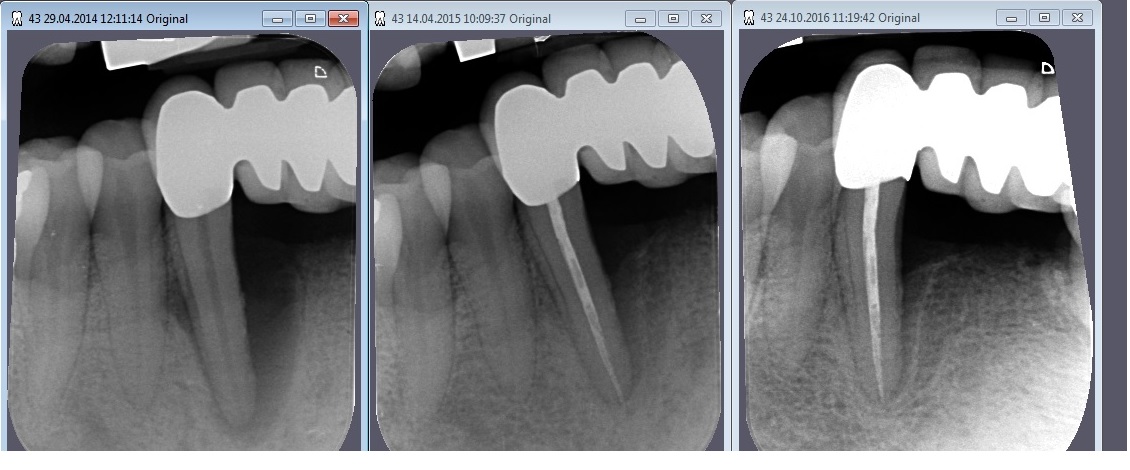

Hat sich der Zahnhalteapparat aufgrund einer Parodontitis abgebaut, kann dieser je nach Ausprägung des Abbaus wieder aufgebaut werden. Idealerweise sollte der neue, wieder aufgebaute Zahnhalteapparat sowohl in der Form als auch in der Funktion die gleichen Eigenschaften besitzen, wie der Ursprüngliche.

Für die regenerative Behandlung ausgeprägter, parodontaler Defekte bieten sich unterschiedliche Methoden an. Es gibt nur wenige Gewebe, die nach einem Defekt in der Lage sind, sich ohne Narbenbildung oder Funktionseinbußen zu regenerieren.

Diese Proteine ermöglichen Ihrem Körper den natürlichen Zahnhalteapparat wieder herzustellen, indem sie die Prozesse, die während der Zahnentwicklung stattfinden, nachahmen. Die Wiederherstellung des Zahnhalteapparats (Wurzelzement, Faserbündel und Knochen) beginnt unmittelbar nach der Behandlung mit Schmelzmatrixproteinen und setzt sich über einen längeren Zeitraum fort.

Durch die Anwendung von regenerativen Methoden mit Schmelz-Matrix-Proteinen soll vermieden werden, dass es zur Bildung von Narben- und Bindegewebe kommt.